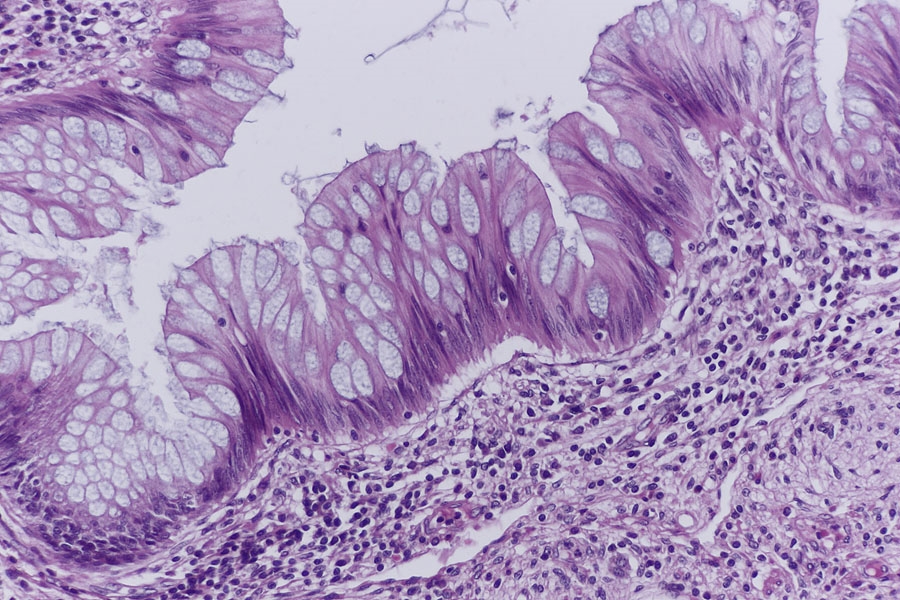

Der dritte Block zeigte dann endlich was auf der Schachtel stand, ein Carcinoid

(rein morphologisch).

Es findet sich ein Darmabschnitt mit einer Mucosa die sehr viele Becherzellen enthält,

so wie einer breiten Submucosa. Auch hier sind die Sekundärfollikel nicht sehr ausgeprägt.

In der Submucosa fallen dann Inseln aus Zellen mit hellem Zytopasma auf (Pfeile) die ich

für Carcinoidzellen halte.

Epithel

In der stärkeren Vergrößerung finden sich dann zahlreiche Carcinoidzellen, die aber auf die Submucosa beschränkt bleiben.

Die Schnitte sind alle HE und an meinem uralten Leitz 1212 Rotationsmikrotom entstanden.

Aufnahmen am Orthoplan mit Cannon 700D und 40mm PanCake.